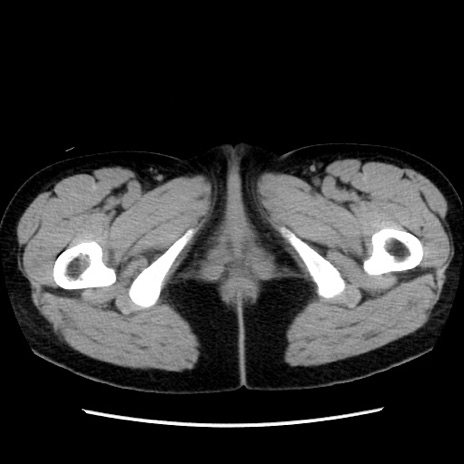

症例10(横断像)

【症例】 50歳代女性

【主訴】 腹痛

【現病歴】前日生レバーを食べた。今朝に排便あり。 昼前に突然発症の腹痛を生じ、当院救急外来を受診した。

【既往歴】 子宮筋腫にてで子宮全摘後

【身体所見】 意識清明、腹部:平坦、軟、下腹部やや左を中心に圧痛・反跳痛あり、筋性防御あり

【データ】WBC 7800、CRP 0.07